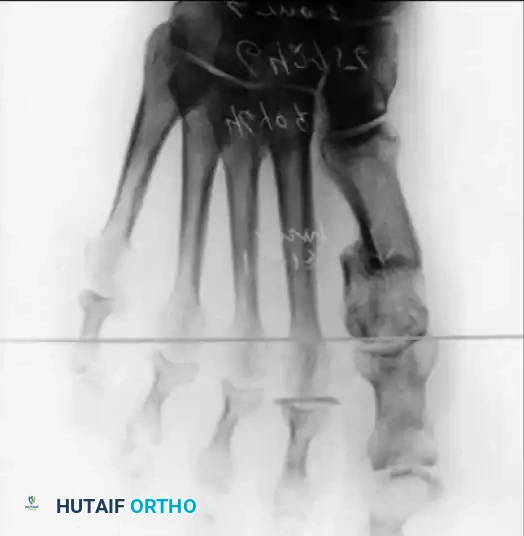

Inadequate vascularity or sensibility should be investigated thoroughly before bunion surgery is considered. In addition, the position of the articular surface of the metatarsal head in relation to the longitudinal axis of the fi rst metatarsal should be determined (Fig. 78-8). Standard preoperative radiographs should include standing dorsoplantar and lateral views, a nonstanding lateral oblique view, and axial sesamoid views (Fig. 78-9). The hallux valgus angle and the fi rst-second intermetatarsal angle should fi rst be drawn on the standing dorsoplantar view by bisecting the shafts of the bones (Fig. 78-10), with an awareness of the normal ranges. These angles are most frequently cited as guidelines for treatment decisions, but Donnelly et al. reported that interobserver measurements of the hallux valgus angle varied by approximately 6 degrees and of the intermetatarsal angle by 4 degrees. They cautioned that potential errors in measurement should be considered when these parameters are used to make treatment decisions. The hallux valgus interphalangeus angle and any evidence of degenerative arthritic changes at the fi rst metatarsophalangeal or metatarsocuneiform joints should be documented. Oddities may be present and, if overlooked, may compromise a technically well-done procedure. Mann emphasized that the presence of an os inter-

(center of the proximal diaphysis) as reference points. They found that measured correction of the hallux valgus and intermetatarsal angles varied by approximately 9 degrees depending on which reference points were used. Recommendations of Coughlin, Saltzman, and Nunley (American Orthopaedic Foot and Ankle Society Ad Hoc Committee on Angular Measurements) included standardized radiographic technique, specifi c placement of reference points (Fig. 78-11), use of a protractor rather than a goniometer for measurements, and, after distal osteotomies, dual measurements using a center-head technique and a Mose sphere.

Fig. 78-10 Method of measuring hallux valgus angle and intermetatarsal angle. Center points are connected, and intersecting lines defi ne angles.

Fig. 78-11 Location of reference points for fi rst and second metatarsals are between 1 and 2 cm from distal articular surface and proximal articular surface of each metatarsal. Because of shorter length of hallux, reference points are placed between 0.5 and 1 cm from proximal and distal articular surface of proximal phalanx. (From Coughlin MJ, Saltzman CL, Nunley JA II: Angular measurements in the evaluation of hallux valgus deformities: a report of the ad hoc committee of the American Orthopaedic Foot and Ankle Society on angular measurements, Foot Ankle Int 23:68, 2002.) support and the medial capsule acting as a spring on stretch. Osteotomy usually is indicated in patients with this medial wedged opening of the joint. If a fi rm forefoot wrap reduces the intermetatarsal angle to a normal value and decreases the hallux valgus angle, however, while congruously rotating the base of the fi rst metatarsal on the medial cuneiform without levering the joint open medially, the McBride procedure can correct the deformity. Correction is improved by excision of the fi bular (lateral) sesamoid because the adductor hallucis and lateral head of the fl exor hallucis brevis are released, markedly reducing the valgus moment at the fi rst metatarsophalangeal joint. In addition, the pull of the fi bular sesamoid on the fl exor hallucis longus through its tendon sheath and pulley system is prevented, reducing another important valgus-producing force on the hallux at the metatarsophalangeal joint. If the fi bular sesamoid is excised, the medial capsule should be repaired with the hallux held in 10 to 15 degrees of valgus. This position must be maintained by a postoperative dressing for 3 or 4 weeks.